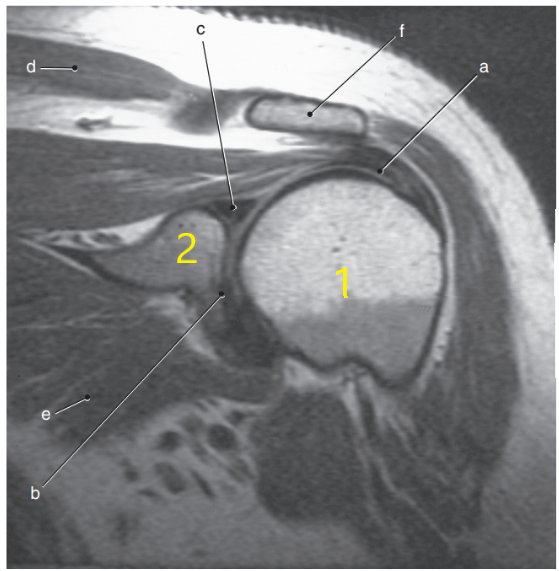

What anatomy is # 2 ?

Scapula

What anatomy is # 1 ?

Humeral head

What is letter c ?

Superior glenoid labrum

Coracoid process

Glenohumeral joint

Acromion Process

Acromioclavicular ligament

What is letter f ?

Posterior glenoid labrum